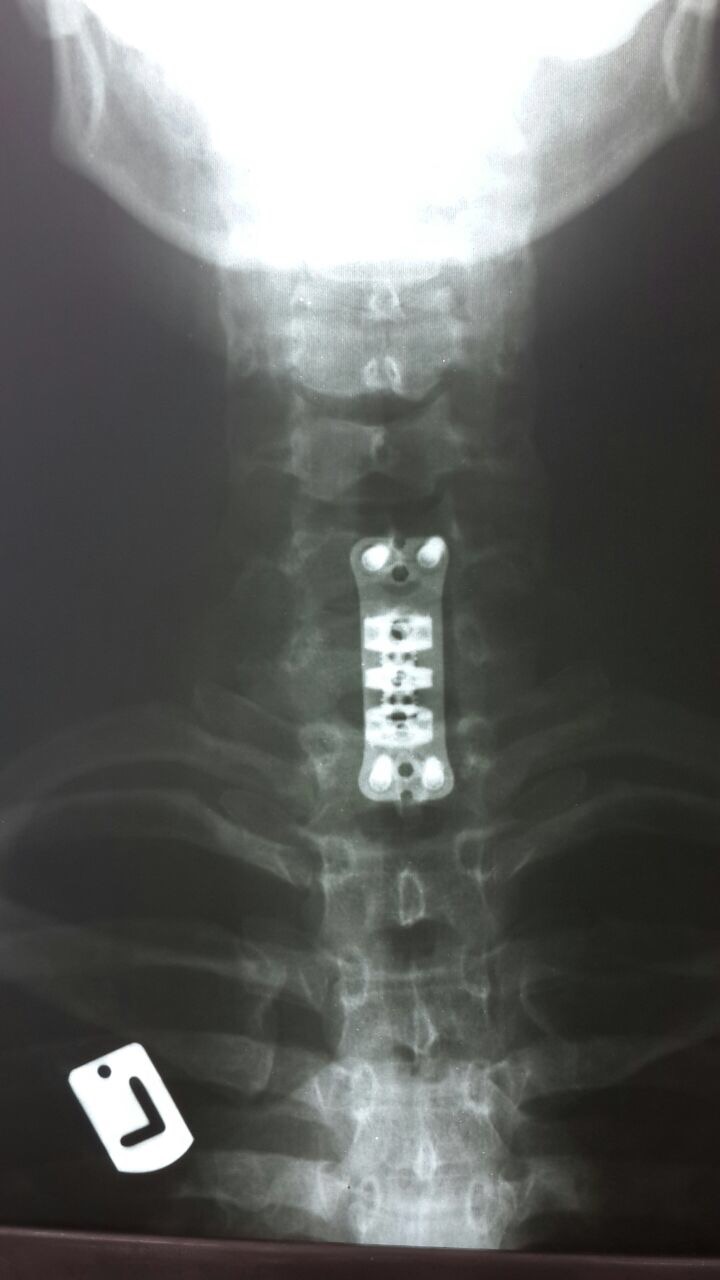

بلافاصله بیمار در بیمارستان شهید بهشتی بندرانزلی توسط دکتر رضا پزشکان (جراح مغز و ستون فقرات) و با کمک دکتر نیک خواه (متخصص بیهوشی)مورد عمل جراحی قرار گرفت.

در این عمل جراحی پیچیده و 4ساعته از گردن به ستون فقرات اپروچ شد و جسم مهره C7گردنی با کمک فرز وبا استفاده از میکروسکوپ به طور کامل تراشیده شد و فشار از روی نخاع گردنی برداشته شد.(کورپکتومی)

سپس برای حفظ پایداری ستون فقرات،بجای جسم مهره C7از مش کیج EXPANDABLE از جنس تیتانیوم استفاده شد.در نهایت یک PLATE بر روی مهره آسیب دیده قرار داده شده و با کمک 4 پیچ روی مهره بالا (C6) و مهره پایین (T1) فیکس شد.